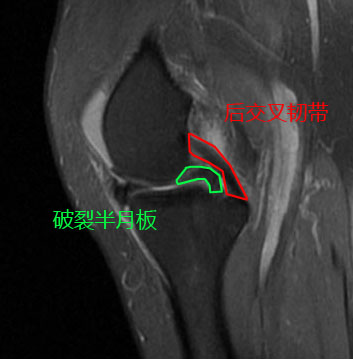

由于已经过去了4年没有再复查核磁,谢医生给她安排了核磁检查,在复查的过程当中我们可以看到非常好的一点是,经历了4年,她的关节软骨还真就没有被破裂的的半月板明显的磨损掉,但是桶柄状的撕裂,没有任何愈合的迹象,在核磁上我们仍然可以看到非常经典的双后交叉韧带征,这说明仍然有大部分的半月板撕裂后,卡在了关节腔内。